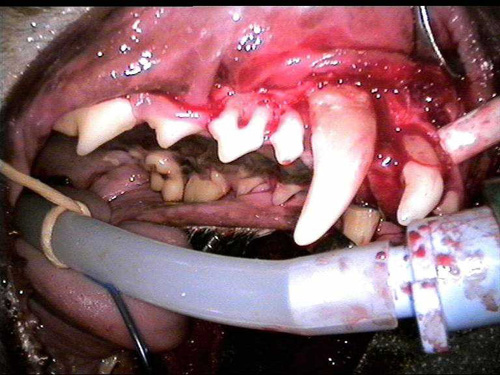

Veterinary Atrocities

cat path 1-4